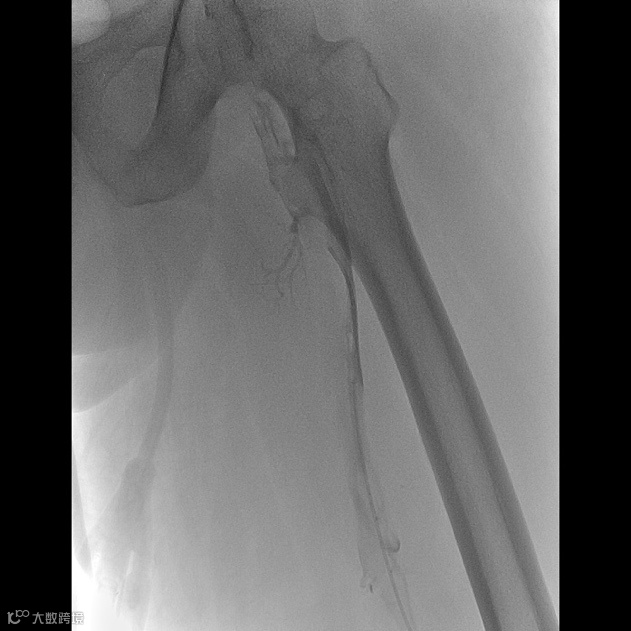

由沈阳市第一人民医院介入科陈建军主任团队运用中天天航™Pro血栓抽吸导管治疗一例急性左下肢深静脉血栓形成且伴有右下肢血流淤滞病变,成功清除血栓并快速恢复肢体灌注,欢迎大家阅读、分享、交流!

手术过程